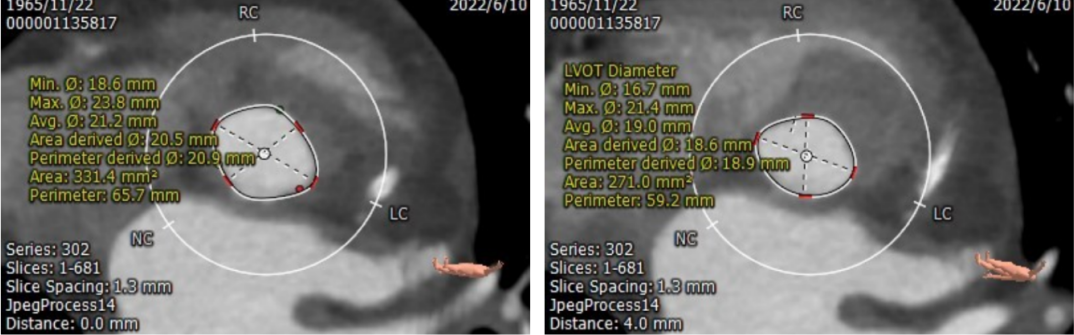

CT测量

主动脉瓣根部CT测量

瓣环周长:65.7mm;LVOT周长:59.2mm

瓣下2mm:20.4mm

瓣下4mm:19.0mm

瓣下6mm:18.8mm

瓣下8mm:19.5mm

• 患者瓣环周长65.7mm;平均直径21.2mm;LVOT周长59.2mm;平均直径19.0mm;